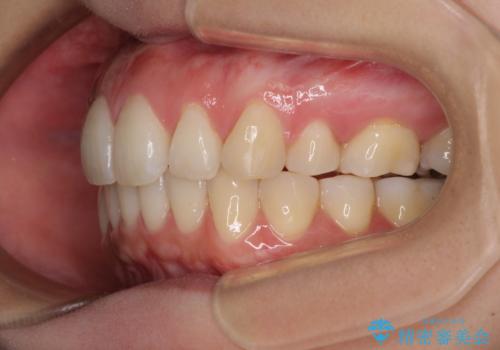

再矯正で突出した口元を引っ込める 抜歯矯正の後戻り

- 抜歯矯正の後戻りで前歯が突出してきていることを気にして来院された患者様です。

口元の突出感を改善するにあたり、抜歯矯正は行うことができないため、奥歯の後方移動とIPR(歯と歯の間を削る)により達成することとしました。

再度後戻りしたときに対応しやすいよう、インビザラインにて矯正治療を行うこととしました。

しっかりと装着時間を守り、ゴムかけにも協力していただいたので、口元を引っ込めることができました。